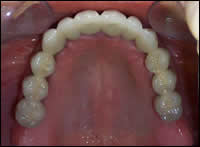

Fig 4 & 5: Pre-operative view of the edentulous maxilla. A 12-unit porcelain bridge was cemented in place.